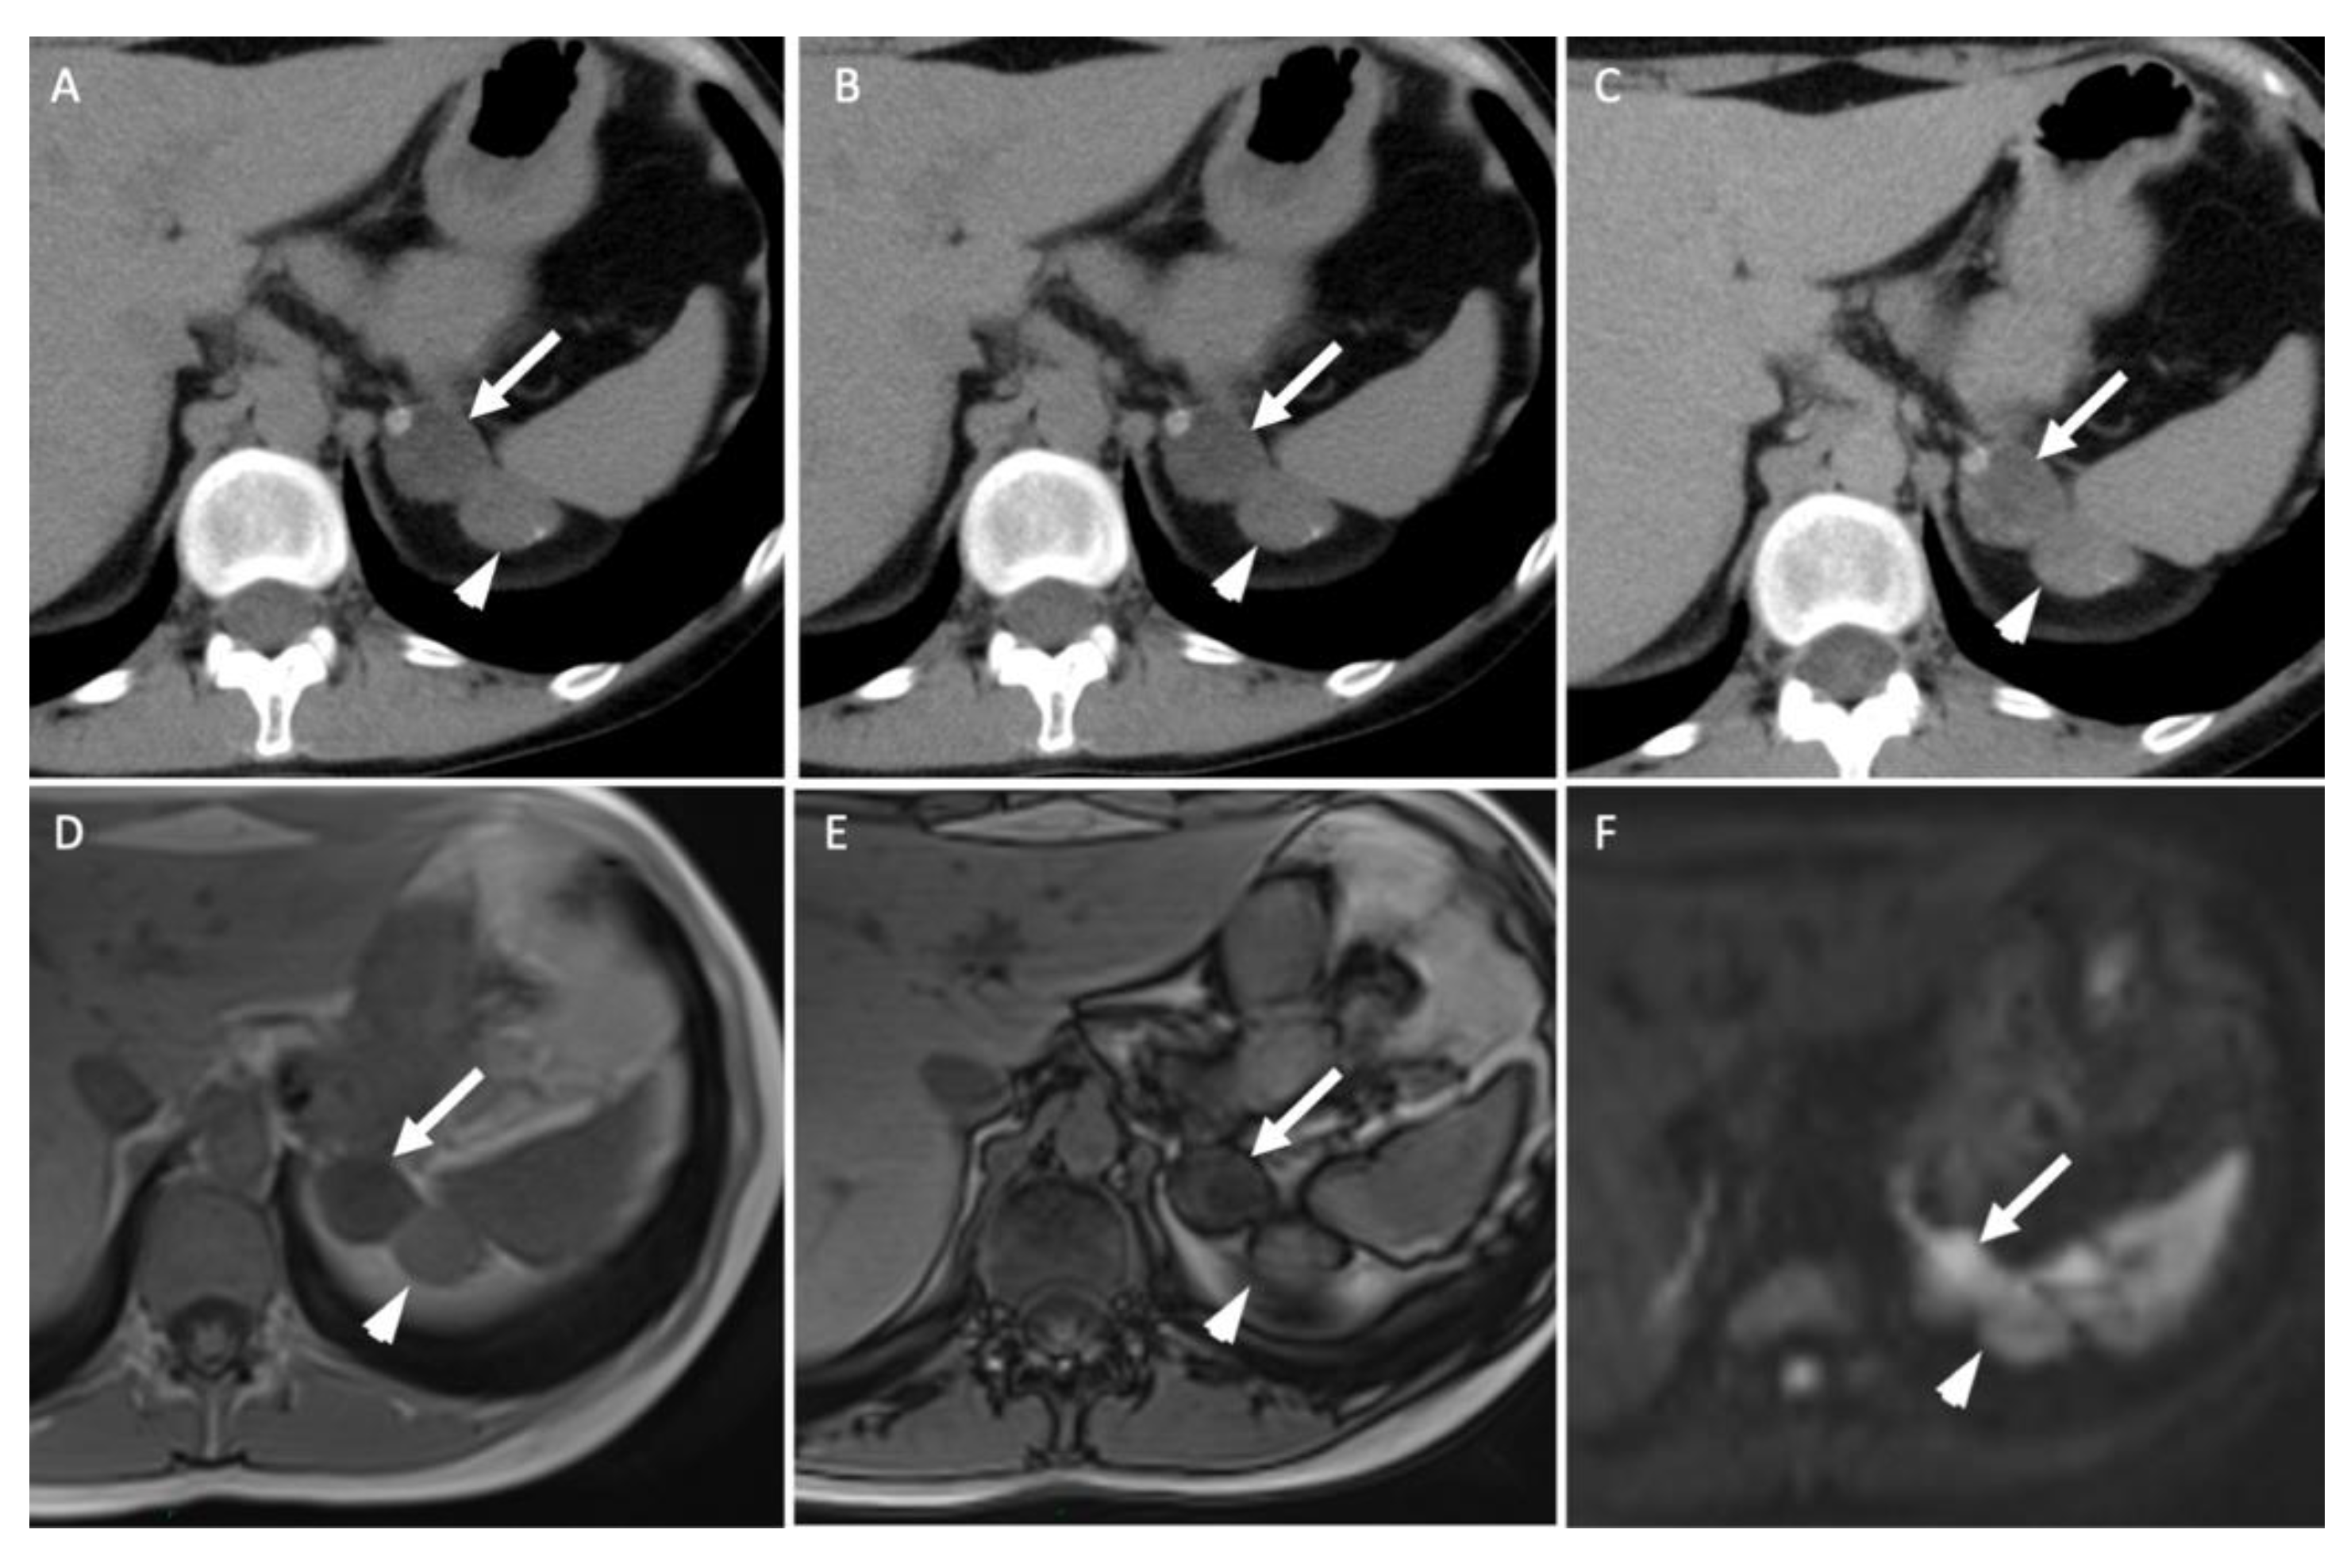

- Kedra, A.; Dohan, A.; Gaujoux, S.; Sibony, M.; Jouinot, A.; Assie, G.; Groussin Rouiller, L.; Libe, R.; Bertherat, J.; Soyer, P.; et al. Preoperative Detection of Liver Involvement by Right-Sided Adrenocortical Carcinoma Using CT and MRI. Cancers (Basel) 2021, 13, 1603. [Google Scholar] [CrossRef] [PubMed]

- Seo, J.M.; Park, B.K.; Park, S.Y.; Kim, C.K. Characterization of lipid-poor adrenal adenoma: Chemical-shift MRI and washout CT. Am. J. Roentgenol. 2014, 202, 1043–1050. [Google Scholar] [CrossRef]

- Haider, M.A.; Ghai, S.; Jhaveri, K.; Lockwood, G. Chemical shift MR imaging of hyperattenuating (>10 HU) adrenal masses: Does it still have a role? Radiology 2004, 231, 711–716. [Google Scholar] [CrossRef]

- Platzek, I.; Sieron, D.; Plodeck, V.; Borkowetz, A.; Laniado, M.; Hoffmann, R.T. Chemical shift imaging for evaluation of adrenal masses: A systematic review and meta-analysis. Eur. Radiol. 2019, 29, 806–817. [Google Scholar] [CrossRef]

- Stanzione, A.; Verde, F.; Galatola, R.; Romeo, V.; Liuzzi, R.; Mainenti, P.P.; Aprea, G.; Klain, M.; Guadagno, E.; Del Basso De Caro, M.; et al. Qualitative Heterogeneous Signal Drop on Chemical Shift (CS) MR Imaging: Correlative Quantitative Analysis between CS Signal Intensity Index and Contrast Washout Parameters Using T1-Weighted Sequences. Tomography 2021, 7, 961–971. [Google Scholar] [CrossRef]

- Romeo, V.; Maurea, S.; Guarino, S.; Mainenti, P.P.; Liuzzi, R.; Petretta, M.; Cozzolino, I.; Klain, M.; Brunetti, A. The role of dynamic post-contrast T1-w MRI sequence to characterize lipid-rich and lipid-poor adrenal adenomas in comparison to non-adenoma lesions: Preliminary results. Abdom. Radiol. (NY) 2018, 43, 2119–2129. [Google Scholar] [CrossRef] [PubMed]

- Miller, F.H.; Wang, Y.; McCarthy, R.J.; Yaghmai, V.; Merrick, L.; Larson, A.; Berggruen, S.; Casalino, D.D.; Nikolaidis, P. Utility of diffusion-weighted MRI in characterization of adrenal lesions. Am. J. Roentgenol. 2010, 194, W179–W185. [Google Scholar] [CrossRef] [PubMed]

- Halefoglu, A.M.; Altun, I.; Disli, C.; Ulusay, S.M.; Ozel, B.D.; Basak, M. A prospective study on the utility of diffusion-weighted and quantitative chemical-shift magnetic resonance imaging in the distinction of adrenal adenomas and metastases. J. Comput. Assist. Tomogr. 2012, 36, 367–374. [Google Scholar] [CrossRef]